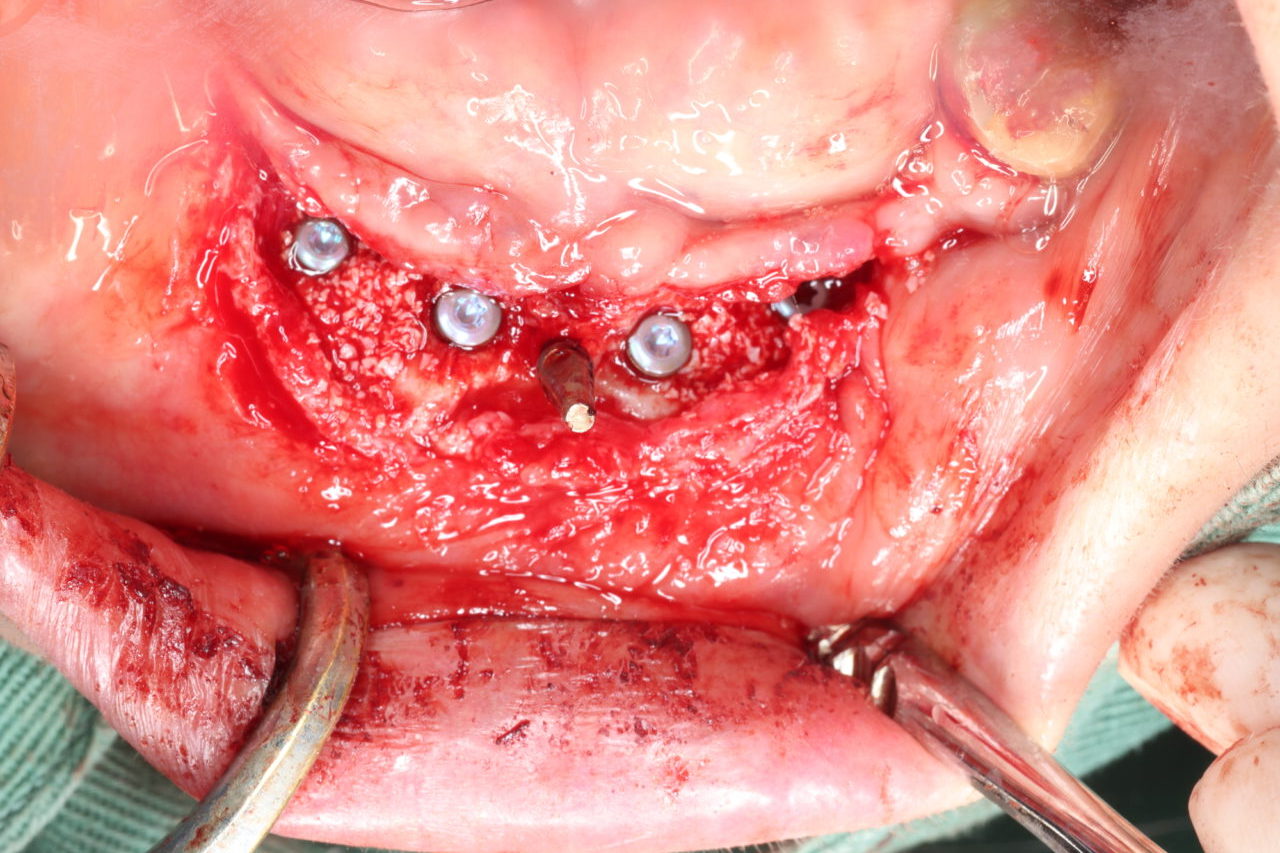

術中写真

6本のインプラントを2回に分けて埋入した。骨の足りない部位には骨増生を行った。

6本のインプラントを2回に分けて埋入した。骨の足りない部位には骨増生を行った。 -